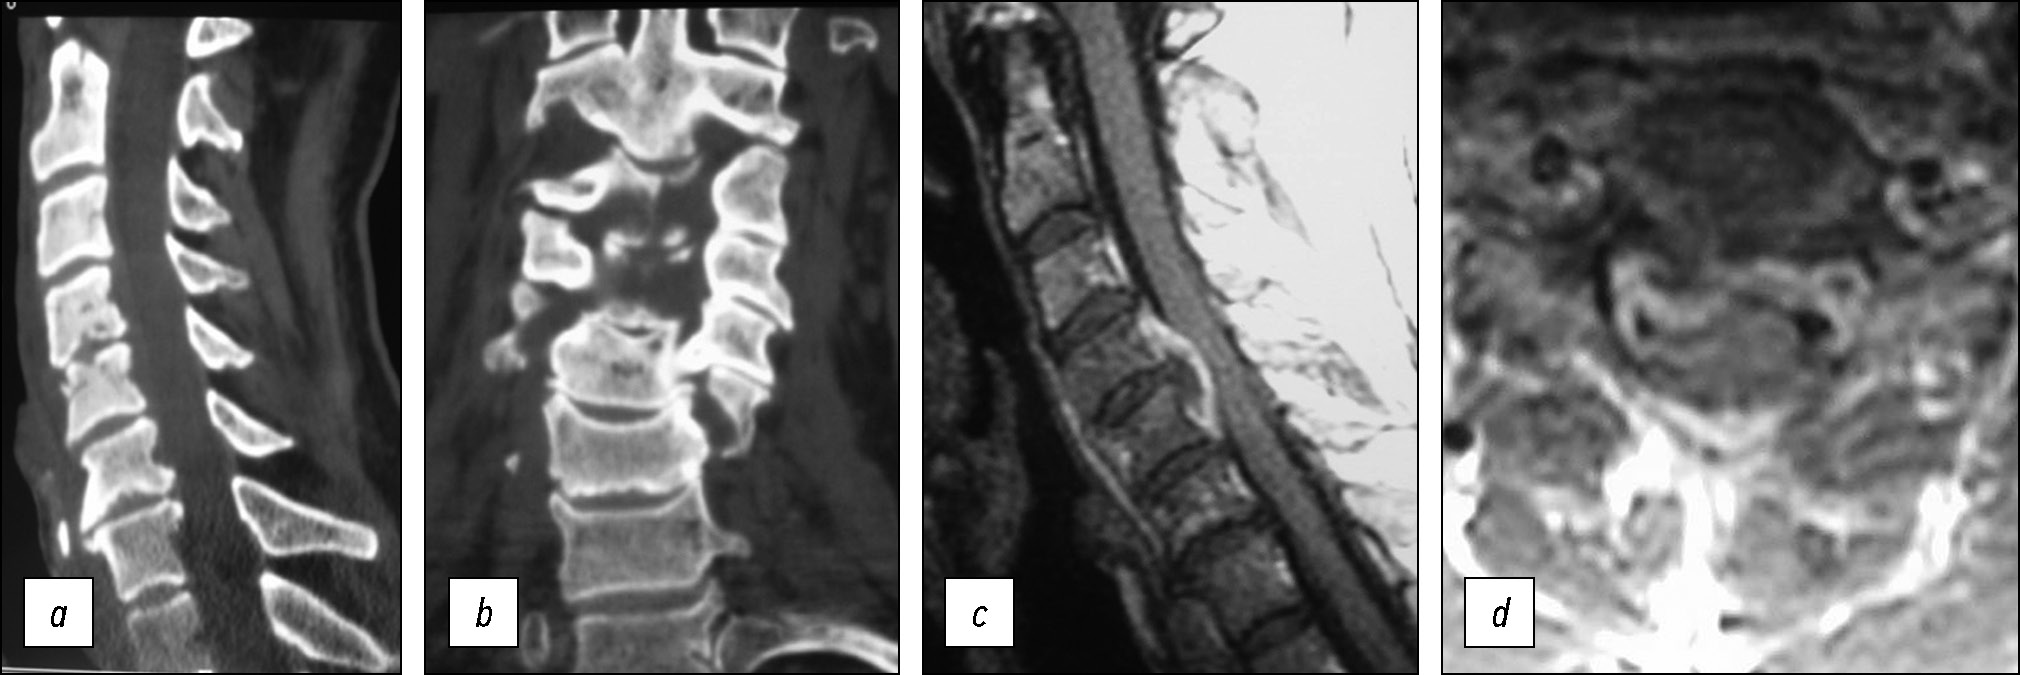

Больной А., 55 лет, поступил с жалобами на слабость во всех конечностях, боли в шейном отделе позвоночника. Болен около 4 месяцев, указывает, что после тяжело и длительно протекающей ангины появилась нарастающая слабость в конечностях. При поступлении клиническая картина заболевания представлена тетрапарезом до 3–4 баллов. Температура тела — 37,5–37,8 °С. В анализах крови отмечается повышение СОЭ до 48 мм/ч. Посев крови отрицательный. По данным КТ (рис. 2а, b) и МРТ (рис. 2c, d) — деструкция тел С4 и С5 позвонков вблизи одноимённого диска, объёмное образование по задней поверхности тел С4-С5 позвонков, вызывающее переднее сдавление дурального мешка, больше справа.

Рис. 2. Спондилодисцит на уровне С4-С5 позвонков. По данным КТ (а, b) выявлена деструкция тел С4-С5 позвонков. На МРТ (c, d) отмечается компрессия спинного мозга на уровне С4-С5 вентрально расположенным эпидуральным абсцессом.

Fig. 2. Spondylodiscitis at the C4-C5. Computer tomography (a, b) revealed destruction of the C4-C5 vertebral bodies. MRI images (c, d) showed spinal cord compression at the C4-C5 level.